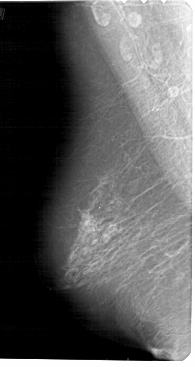

A_1457_1.LEFT_MLO

LEFT_MLO LINES 5491 PIXELS_PER_LINE 2911 BITS_PER_PIXEL 12 RESOLUTION 43.5 NON_OVERLAY